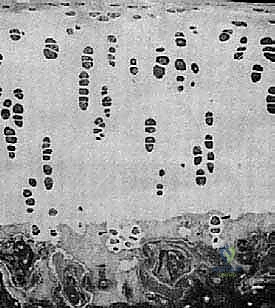

Microscopic Architecture

Articular cartilage is an intricate, highly specialized connective tissue, devoid of blood vessels, nerves, and lymphatic channels. Its metabolic needs are met primarily by diffusion from the synovial fluid. Histologically, it comprises four distinct zones, each with unique structural and functional characteristics:

- Superficial (Tangential) Zone: This outermost layer, parallel to the articular surface, contains flattened chondrocytes and collagen fibers oriented parallel to the surface. It's crucial for resisting shear forces and providing a smooth gliding surface.

- Middle (Transitional) Zone: Here, chondrocytes are more rounded, and collagen fibers are obliquely oriented. This zone absorbs compressive forces.

- Deep (Radial) Zone: Characterized by chondrocytes arranged in columns and collagen fibers oriented perpendicularly to the articular surface. This layer is vital for resisting compression and anchoring the cartilage to the subchondral bone.

- Calcified Zone: The deepest layer, adjacent to the subchondral bone, where the matrix is calcified. It's separated from the deep zone by the "tidemark," a critical anatomical boundary that defines the interface between cartilage and bone.

The chondrocyte, constituting only about 5% of the cartilage's weight, is the sole cell type responsible for maintaining the metabolic balance of the extracellular matrix. These cells synthesize and secrete the primary components:

- Water: Approximately 75% of cartilage weight, it's a critical component for hydration and load distribution.

- Collagen: Predominantly Type II (about 10% of weight), it provides the structural framework and tensile strength.

- Proteoglycans (Glycosaminoglycans): Around 10% of weight, these highly negatively charged molecules trap and hold water, imparting the tissue's compressive stiffness and resilience.

FIG 2 • A. Histology of articular cartilage.